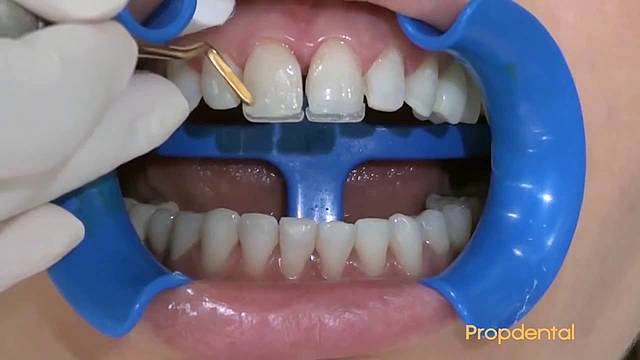

• Carillas directas.

Carillas directas.

Elaboración de carillas directas de los OD. 1.5 - 2.5.